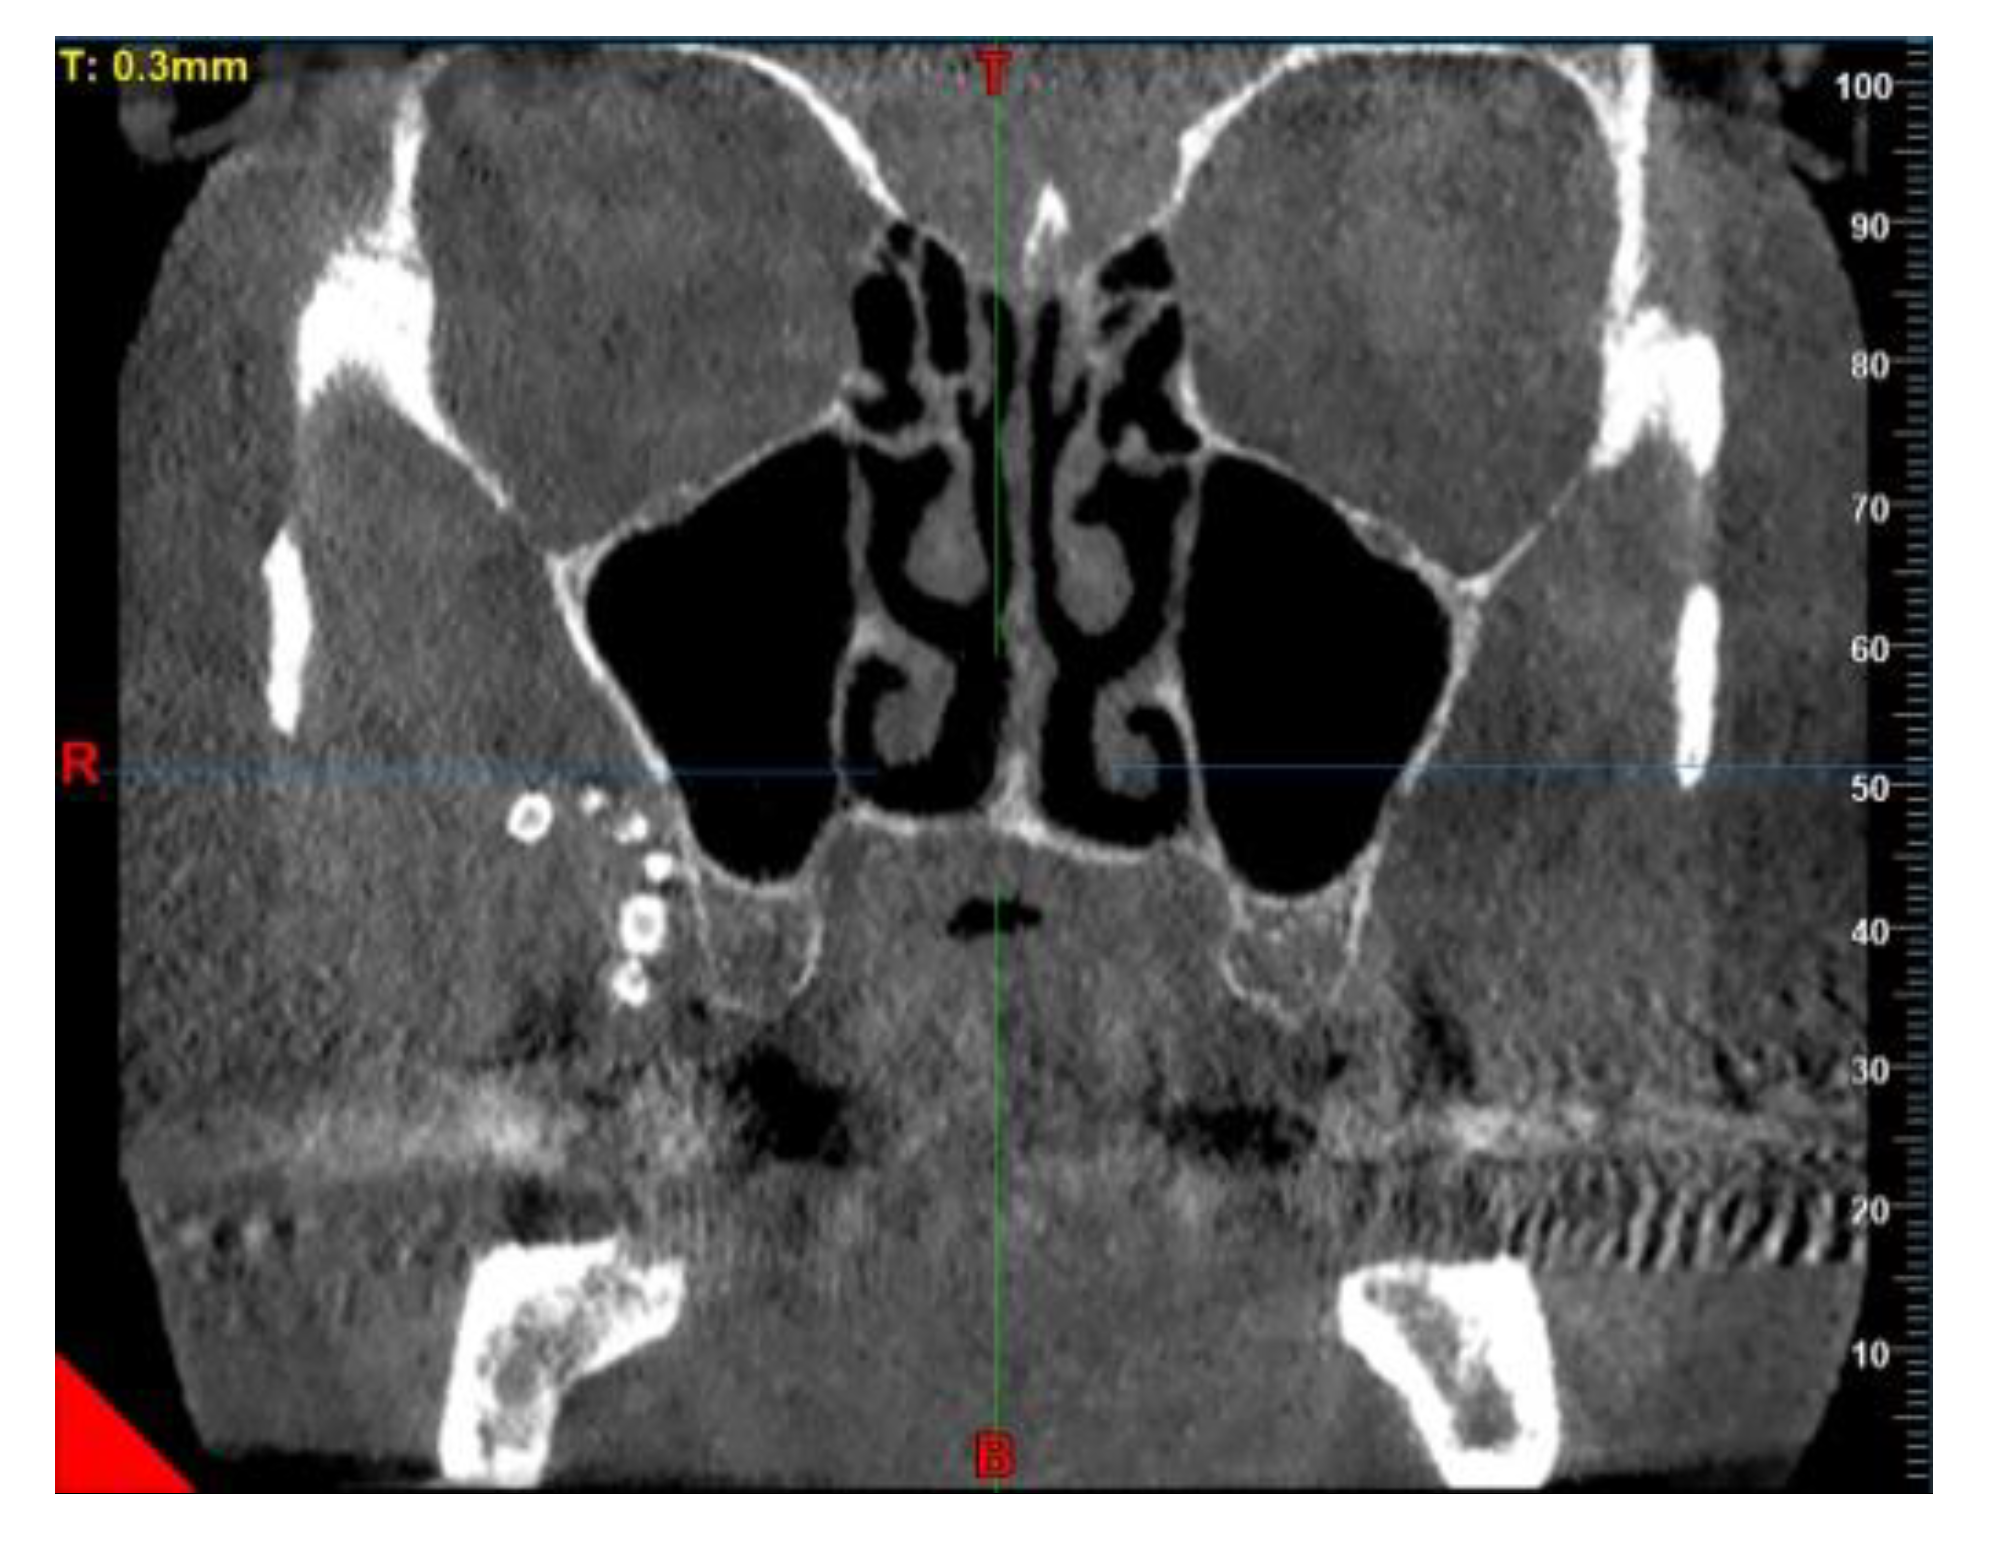

2. Case Presentation